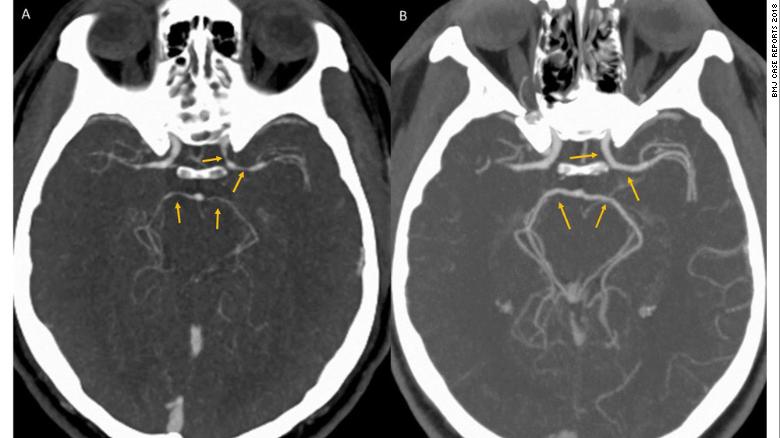

Hình ảnh chụp CT não bộ của người đàn ông ở Bệnh viện Henry Ford, Mỹ. (Ảnh: CNN)

Bệnh nhân không có bất cứ sự tổn hại về thần kinh nào hay có triệu chứng của một cơn đột quỵ não. Hình ảnh chụp CT cũng loại trừ việc anh này có cục máu đông hoặc bị chảy máu trong não.

Theo các bác sĩ điều trị, thông qua ảnh chụp CT, họ phát hiện ra một điều lạ lùng: Các động mạch cảnh bên trái và bốn mạch máu khác cung cấp máu cho não đều bị thu hẹp hơn so với người bình thường.